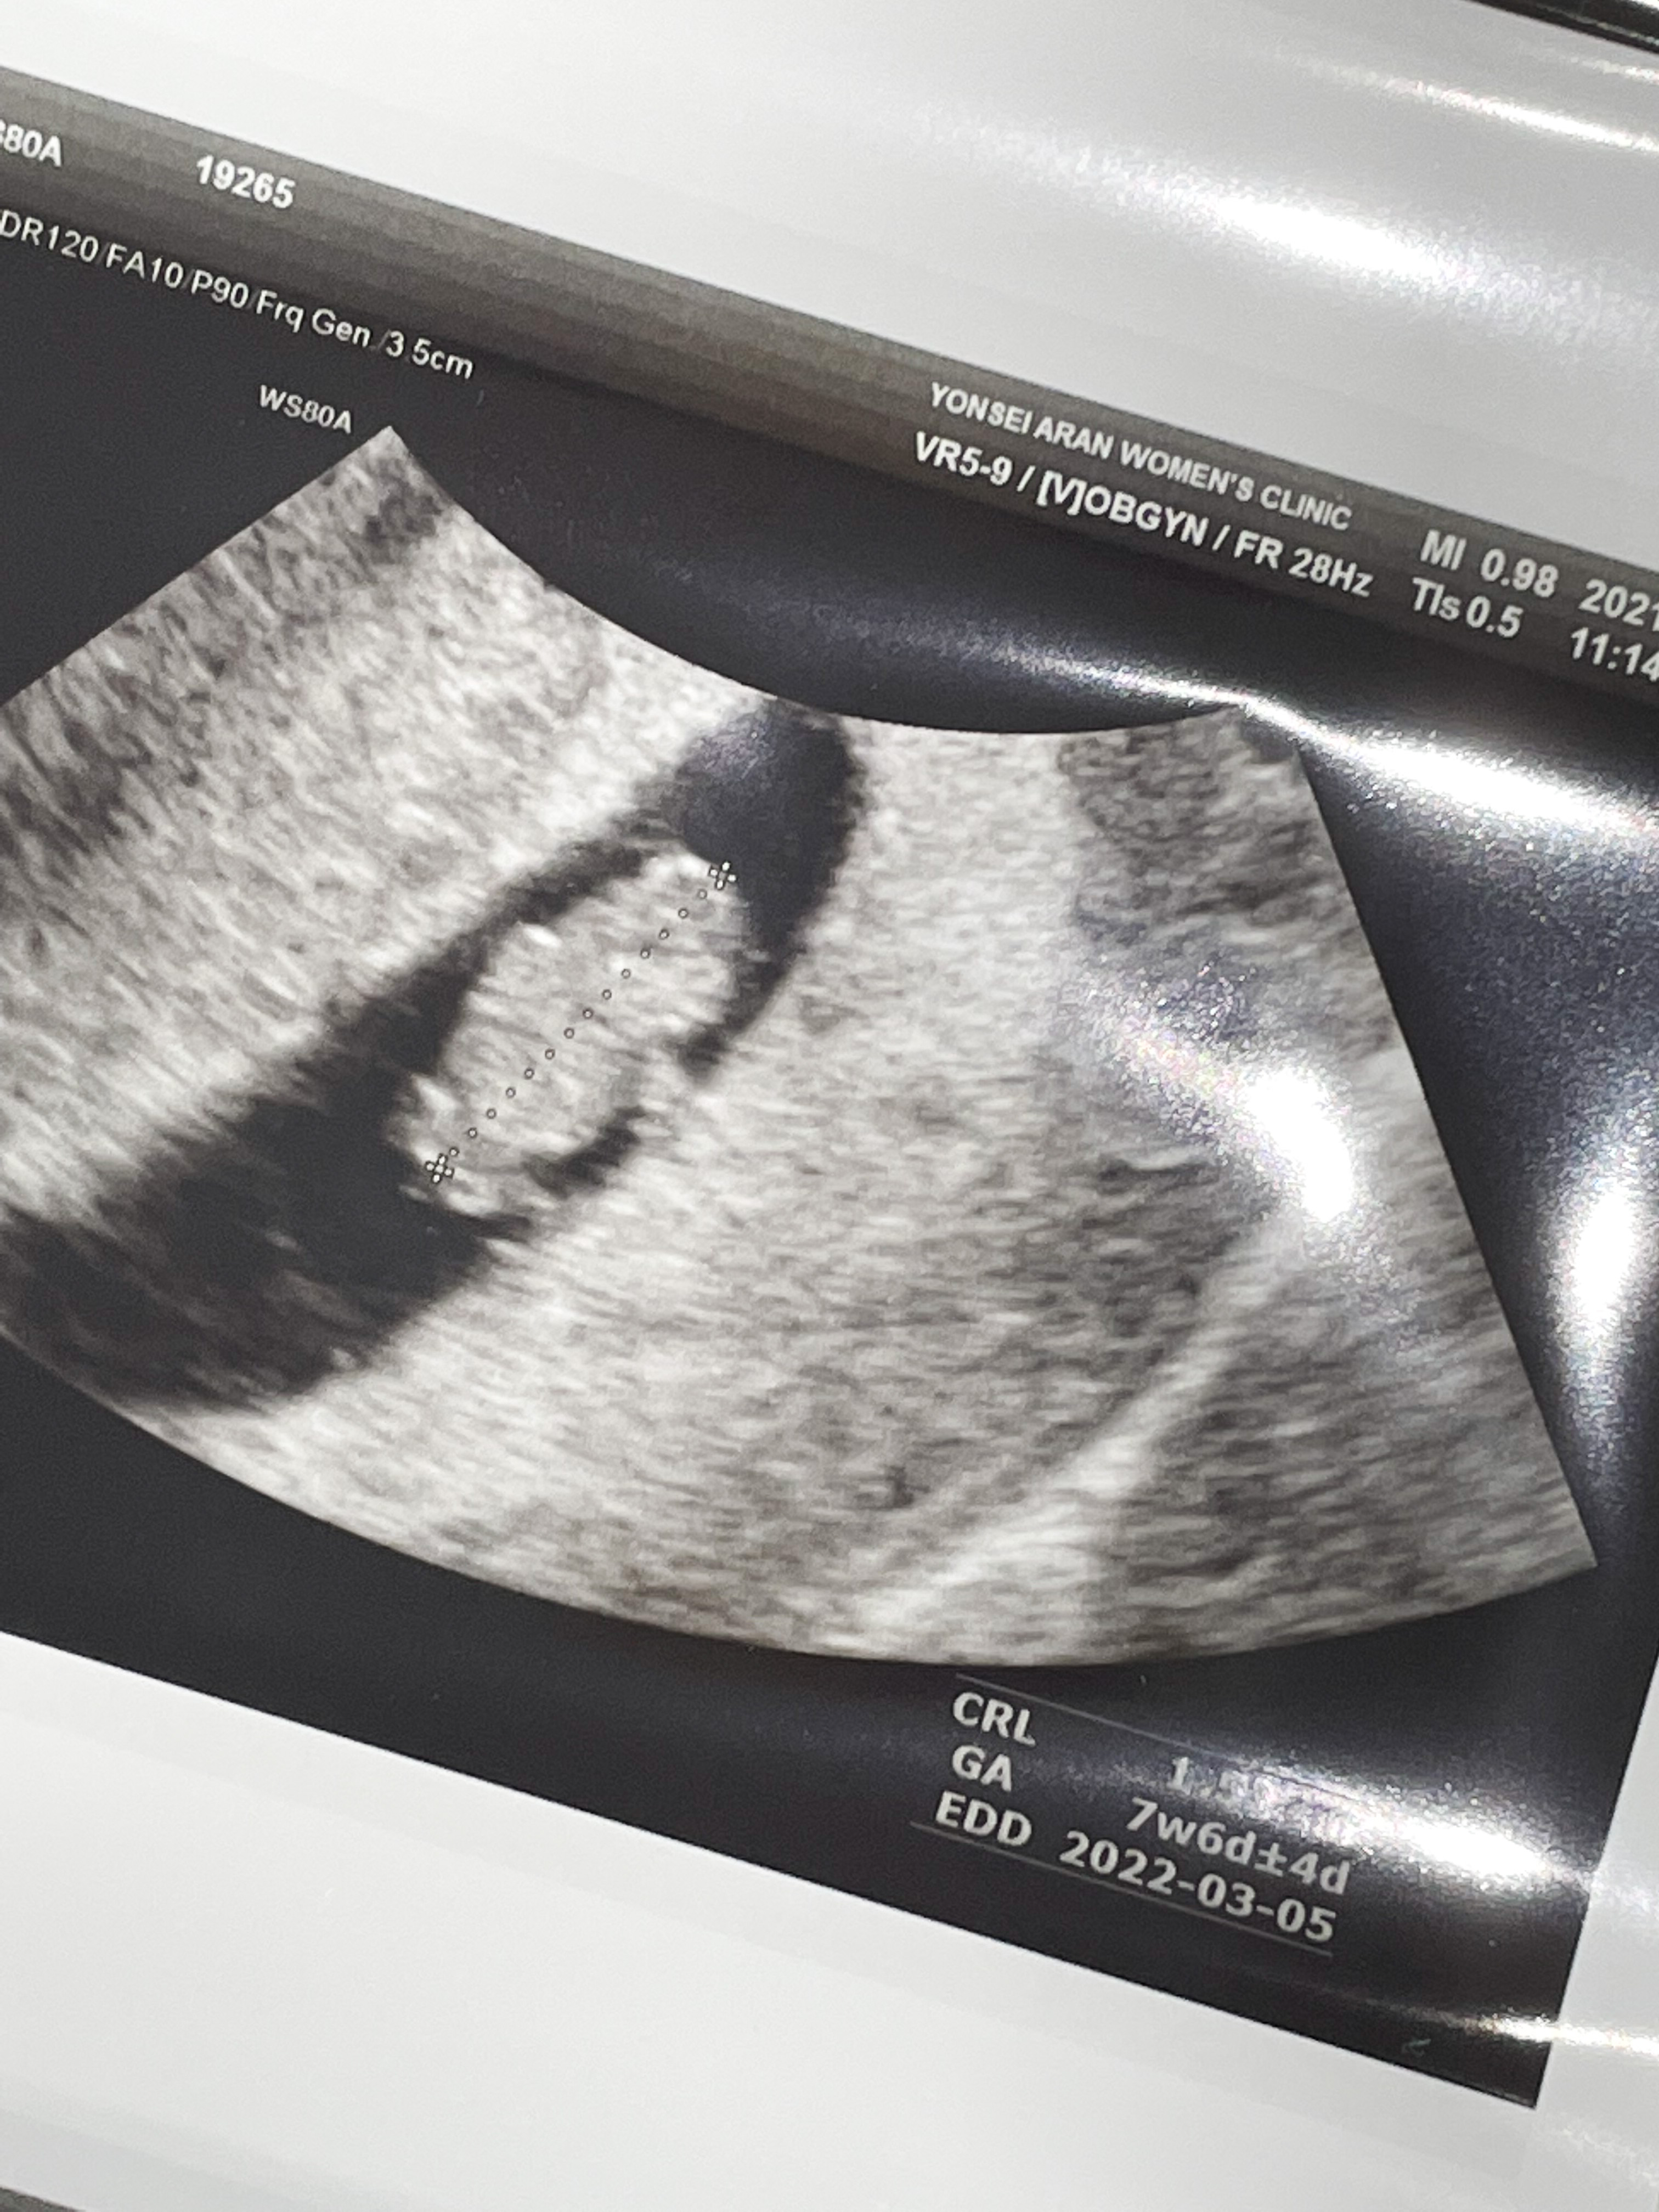

8주 1일

입덧약 처방 받으러 간 김에 초음파도 한 번 봤다.

막대기 같이 생겼던 아기가 어느덧 통통해졌고 팔다리까지 있었다.

쌤이 젤리곰이라고 너무 귀엽다고 하셨는데,

내 눈에는 물개 같았다.

심장도 잘 뛰고 있었다.

뇌 쪽이 구멍이 뚫려 있었는데 정상이라고 하셨다.